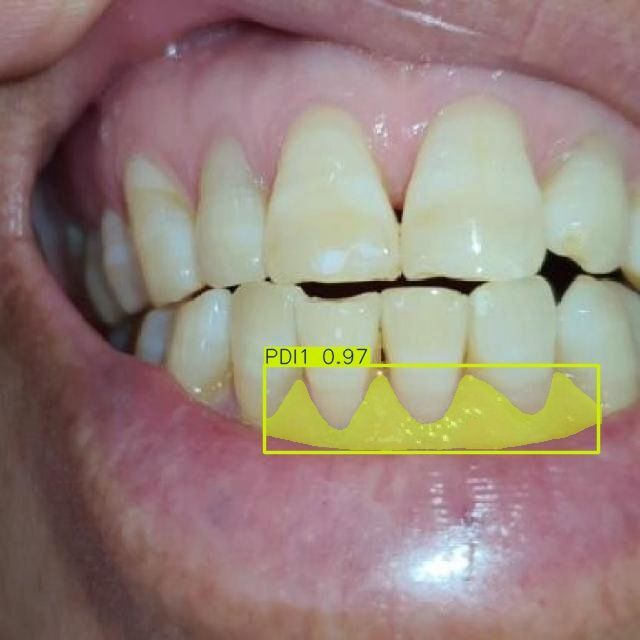

Мы проводим discovery-фазу для нашего клиента (стоматологическая клиника в Москве) и создали работающий прототип ИИ-сервиса, который автоматически сегментирует зубы и связанные патологии по 10 специализированным классам на стоматологических изображениях. Решение построено на Ultralytics YOLOv11-seg, обучено на пользовательском датасете и ускоряется на GPU (CUDA). Прототип уже демонстрирует корректную сегментацию и классификацию по классам кариеса, состояниям десен и показателям пародонта, что открывает путь к автоматизированной диагностике, системам поддержки клинических решений и оценке состояния зубов в реальном времени.

- Пародонтальные индексы: PDI1, PDI2, PDI3